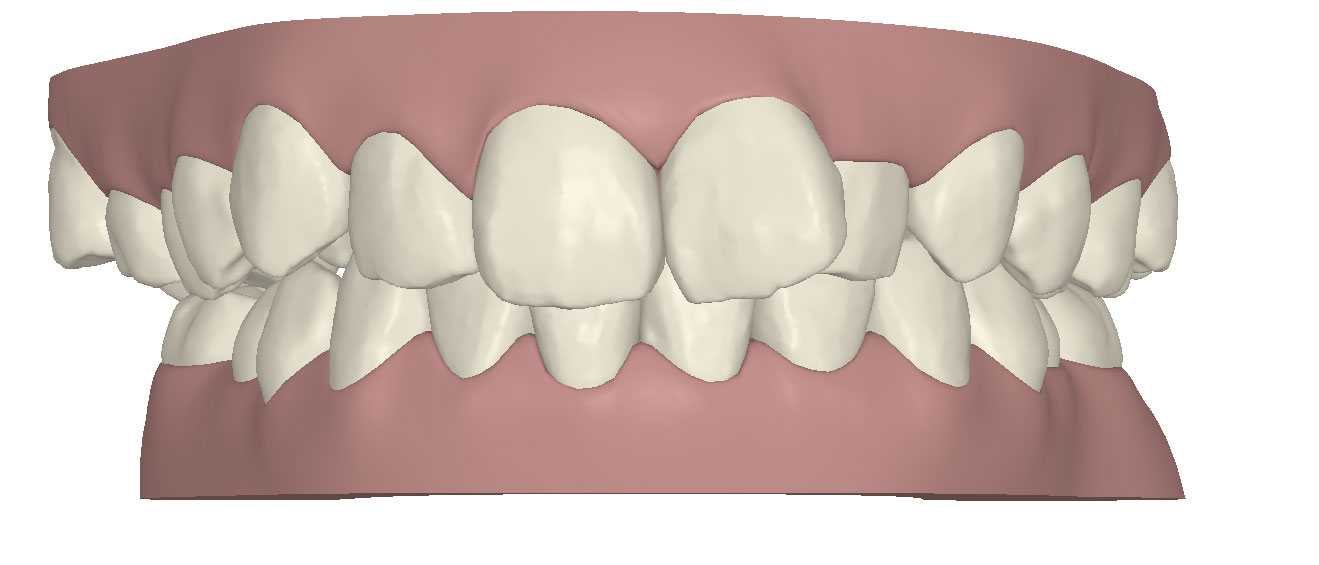

コンピューターを使って作製した透明なマウスピース型の矯正装置(アライナー)を段階的につけ替えていき、それにより歯列を矯正し、歯並びへと改善します。はじめに 治療開始から終了までのアライナーができあがってきます。マウスピース型矯正装置(インビザライン)の最大の特徴として「クリンチェック」というソフトがあります。3D のコンピュータ シュミレーション画像で、治療開始から完了までを目で見て確認することができます。

マウスピース型矯正装置(インビザライン)治療においては、クリンチェックというシミュレーションソフトを活用しております。

このクリンチェックの魅力は、治療前の現在の歯並びから治療後の歯並びを視覚化して患者様にご説明できる点にあります。

また、抜歯・非抜歯、全体矯正・部分矯正などそれぞれの治療パターンをシミュレーションすることが可能です。

| 治療前 |  |

| ライトプラン 隣接面削合なし |

| ライトプラン 隣接面削合あり |

| フルプラン 隣接面削合あり |